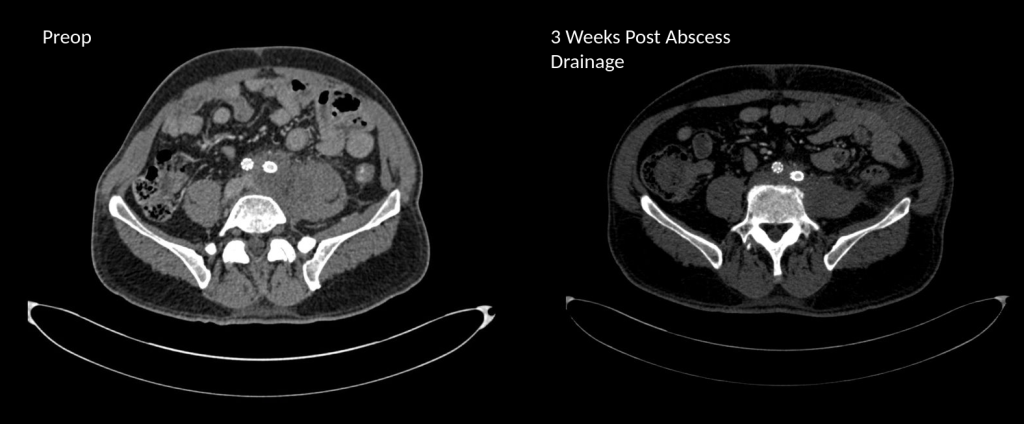

As a vascular surgeon, I perform operations in the traditional open fashion, and endovascular procedures which are a done with imaging from x-ray. Occasionally, I do laparoscopic surgery. The open surgical procedures include operations on the aorta and its branches, and on arteries in the legs, arms, and neck. I also work on veins throughout the body. The patient arrives with a set of conditions, a prior history, and an examination, and given a problem, you evaluate it with various tests which can be blood tests, vascular tests, imaging studies like X-ray, Ultrasound, Vascular Lab Studies, CT scans and MRI’s. This is called the workup -getting data to plan a procedure. Knowledge of anatomy and physiology and biomechanics of flow are crucial to put together a plan that will be successful in treating the disease with low complication rate and good durability. The procedures require a great deal of planning and often I include my colleagues within my department and those in other specialties to get their insights for making a plan that accounts for the reason for operation, plan for operation, contingency plans, and recovery in the hospital, and healing outside the hospital. You can see some of these cases on my blog, vascsurg.me.